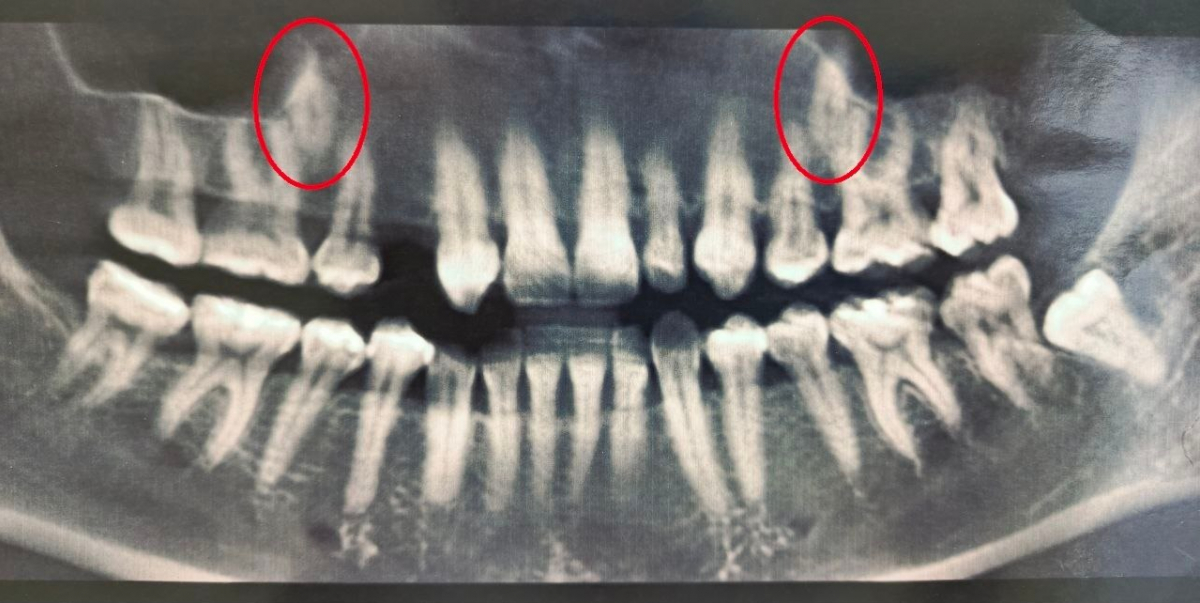

Диагностика с помощью компьютерной томографии показала сложную картину – в челюсти находились два непрорезавшихся зуба.

При этом, в самом зубном ряду был дефект – один зуб полностью отсутствовал, а другой был сильно меньше нормы.

Врачи приняли решение «вытянуть» непрорезавшиеся зубы и поставить их в ряд, в правильное положение.

На сегодняшний день один зуб уже полностью вышел из костной ткани и занял свое законное место. Второй успешно проходит последний барьер - кортикальную пластинку челюсти - и вскоре тоже встанет в ряд.